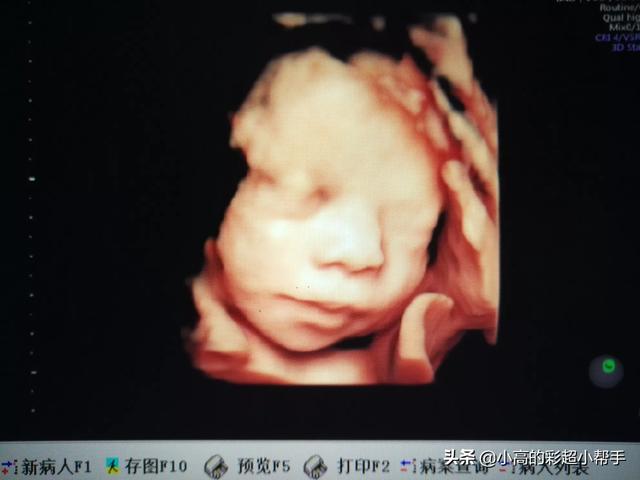

1、首先四维彩超主要检查面部畸形:四维彩超检查时重点观察胎儿双眼与眼眶是否等大、等圆,以及眼距测量,硬腭、软腭及上唇弧型曲线是否连续中断等。接下来筛查胎宝宝的颈部,看是否有异常包块。

4、检查中,检查者会严谨地观察胎头形态、脑组织(丘脑、小脑、小脑蚓部、颅后窝池、侧脑室)以及中线距两侧颅骨板的距离等,筛查无脑儿、露脑、脑积水等情况。

还有四维彩超可以记录宝宝的第一次有照片的容貌,也算是宝宝人生的第一张照片,运气好的话还是带微笑的照片,这个很有纪念意义。